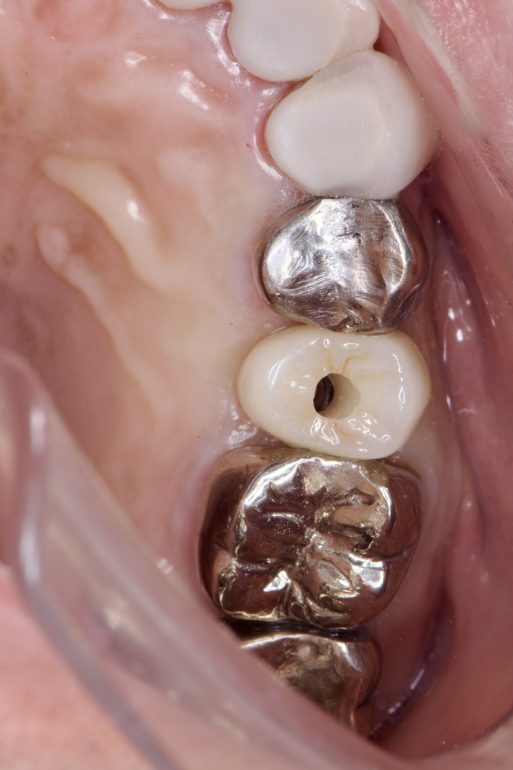

奥歯のインプラント😬✨

こちらの患者様は、他院にて治療途中だった箇所の根管治療に始まり、以前抜歯された箇所にインプラントを入れられました。

↓根管治療中のお写真です

根管治療を終えた後、ジルコニアの被せ物をしました醴

そして残るはインプラントオペです!

インプラントを埋入する際は、サージカルガイドを使用しました。

インプラントのオペ後、3ヶ月ほど経過し、最終的にジルコニアの被せ物をしました。

とても綺麗です✨

患者さんもしっかり噛めて嬉しいと喜んでいました。見た目も満足していただけました。